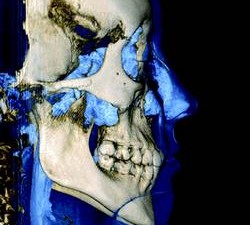

3-D software can shade images to differentiate varying densities of facial structures. Grayscale shading provides the ability to view the relationships of common internal anatomy. Traditional CT imaging renders an 8-bit grayscale (256 shades) or 12-bit grayscale (4,096 shades). Present-day scanners render images in 14-bit grayscale, providing 16,384 shades. Color coding the image by density further distinguishes anatomical structures, enabling the clinician to view pertinent anatomy while planning implant cases, such as nerves and nasal cavities, and mandibular and maxillary dimensions. Segmentation literally cuts the volume rendering, conceding top views, side views, and CT slices that produce unlimited axial, coronal and sagittal views. CBCT slices are as thin as 0.1 mm, compared to 1 mm for a conventional fan CT scan.

CBCT imaging provides comprehensive data and the ability to dynamically manipulate that data, viewing anatomy from multiple perspectives. Diagnosis of TMJ condition and disorder or jaw pathology along with the evaluation of orthodontic cases, airways, impacted teeth and periodontal defects are all facilitated through the use of CBCT imaging.